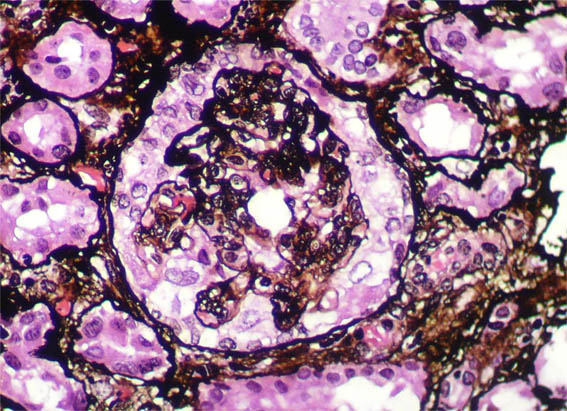

Figure 7.

Methenamine-silver stain, X400.